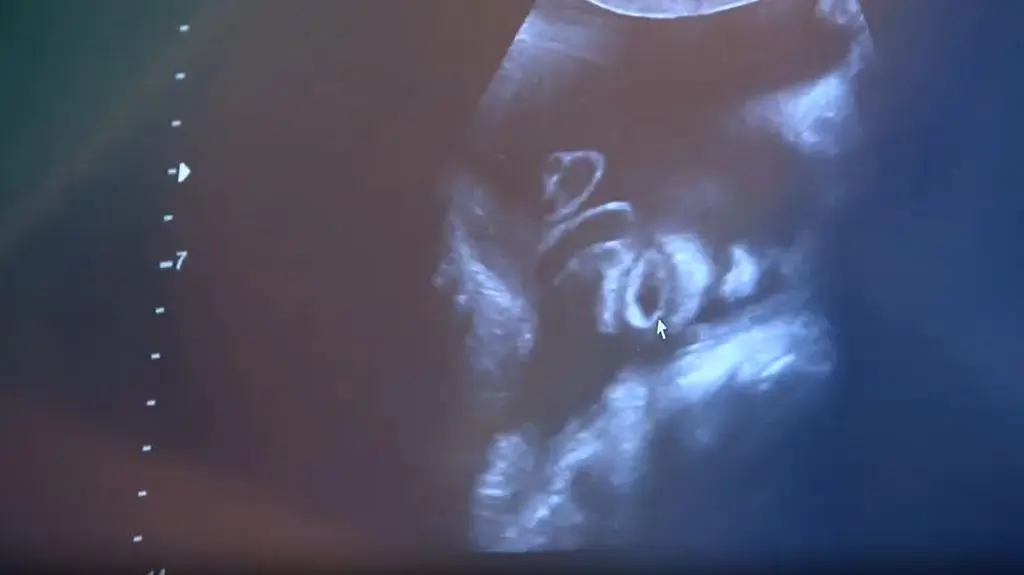

Koalicja Obywatelska i Lewica chcą zmian w prawie aborcyjnym